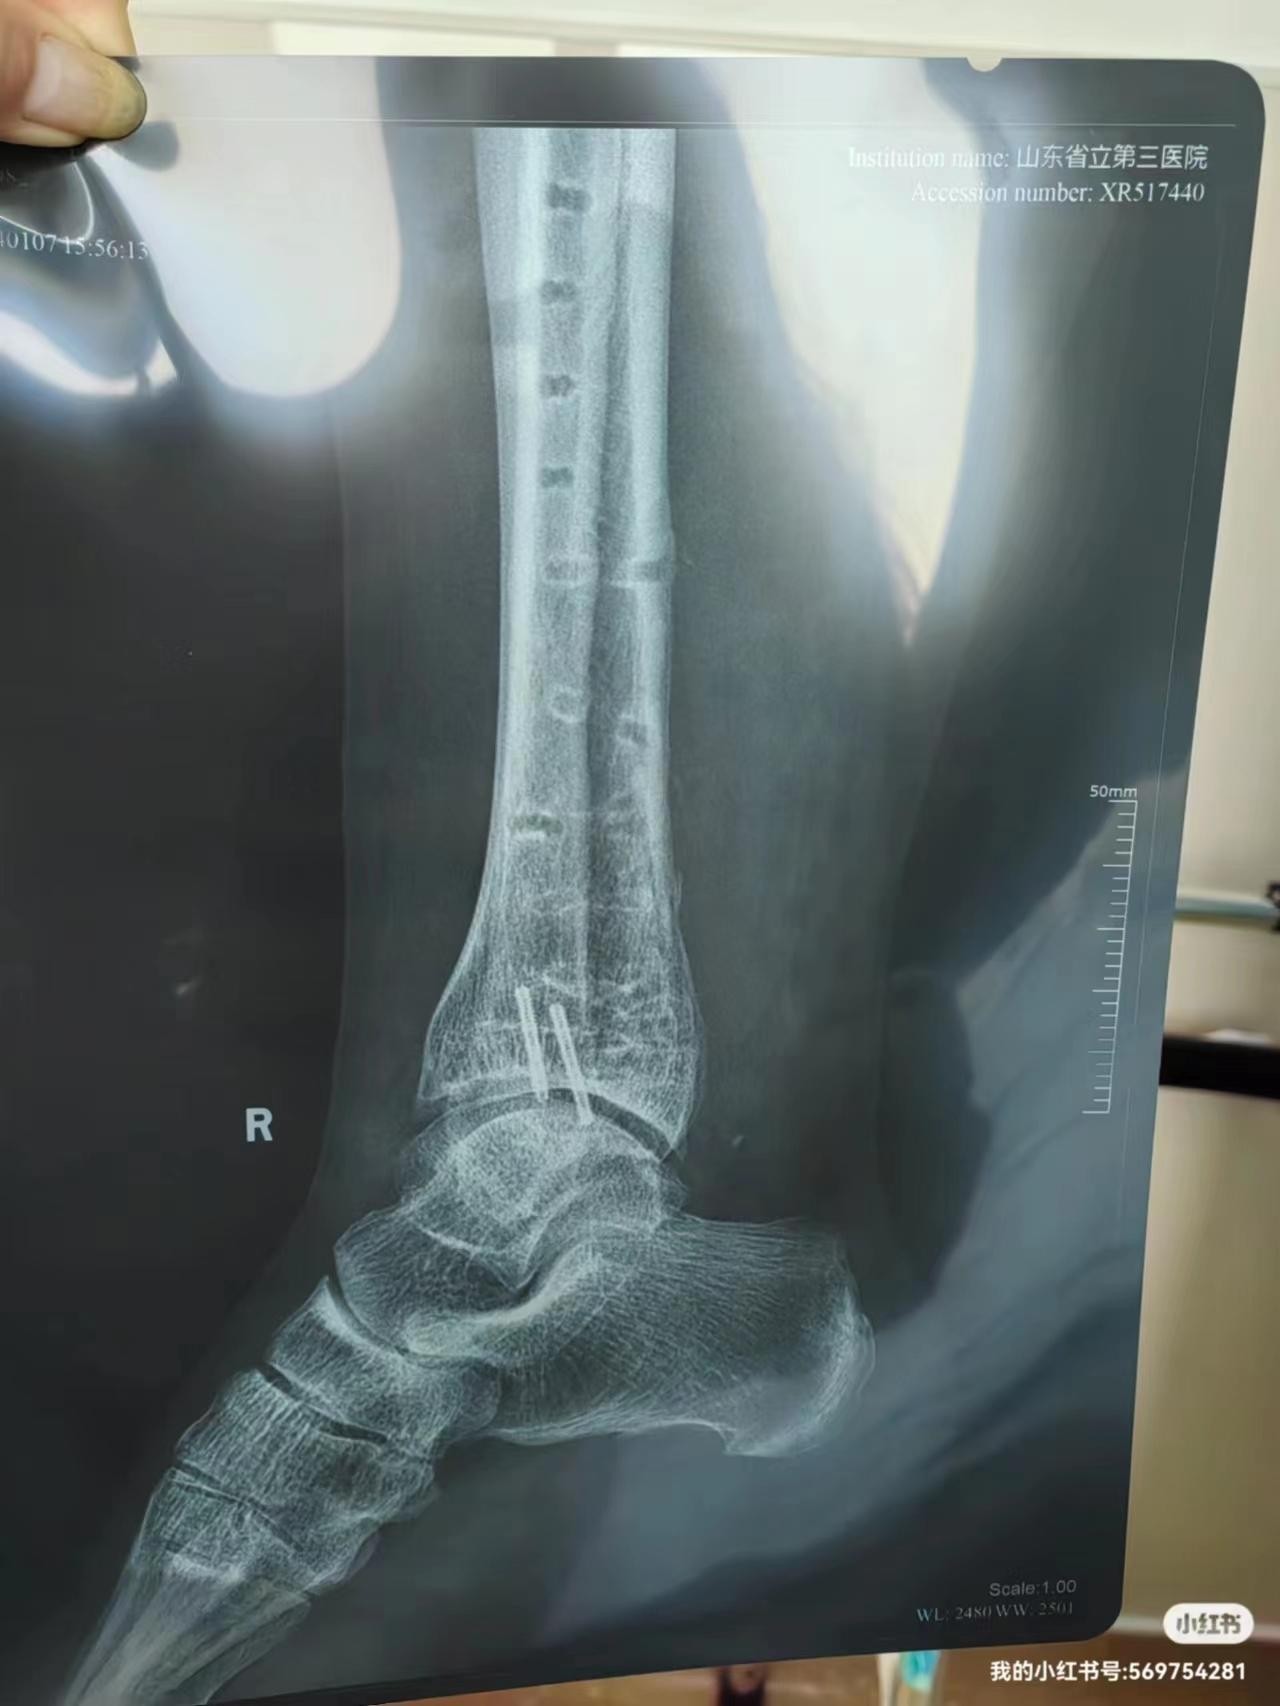

这次取出了右脚踝的三块钢板和N多钢钉,骨头上布满小洞洞,跟洞洞鞋似的,还有两个钉子断在了里面,要强行取出还得搓骨,想想算了吧,不但伤骨头,还会让两个半小时的手术时间再增加三四个小时,就让它俩永远陪着我好了!